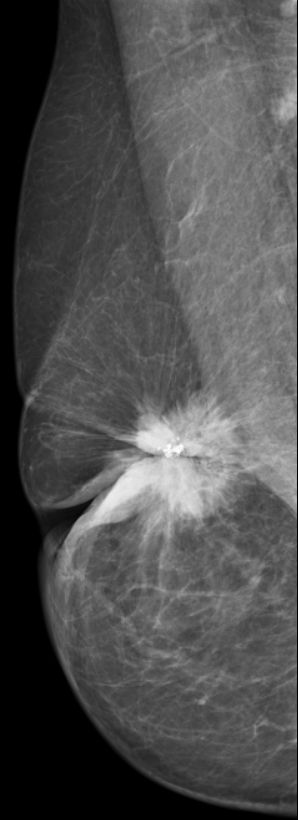

12mm großes invasives duktales Karzinom G3. Spotkompression.

| ||